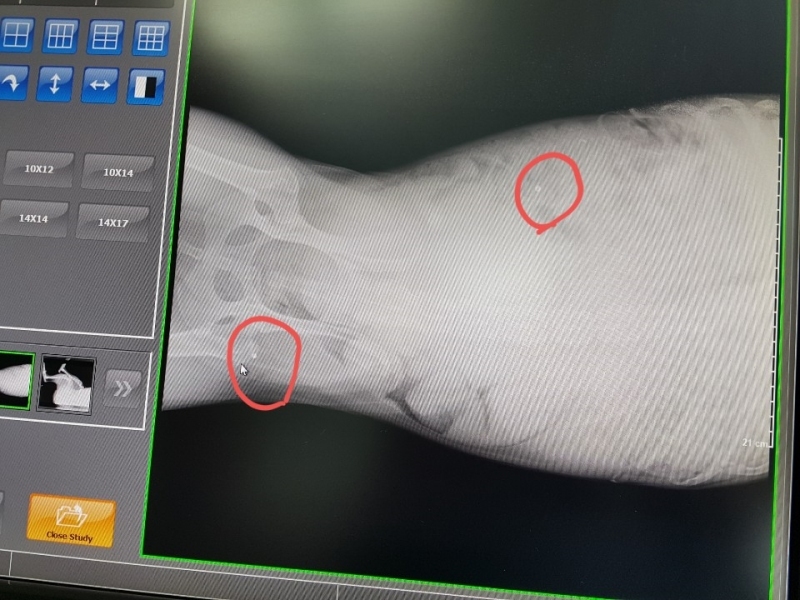

¿À´Ã ¼º³²¿¡ Àִ µ¿¹°º´¿ø¿¡ °¡¼­ ¿¢½º·¹À̸¦ Âï¾îº» °á°ú

½ÇźÀÌ ¿©·¯¹ß ¹ÚÇôÀִµ¥  ¼ö¼úÀ» ¸øÇÏ°í ¸Ô´Â°ÍÀº Àß ¸ÔÀ¸´Ï

°ßÀÌ ¸Ô´Â°Íµµ À߸԰í Ȱ¹ßÇѵ¥  ¿ÞÂÊ ¹ß¸ñÀ» ¾²Áö ¸øÇÕ´Ï´Ù,

¿ÞÂÊ´Ù¸® ¹ß¸ñ¿¡ ½ÇźÀÌ ¹ÚÇôÀִµ¥ »À¸¦ ¸Â°í ½ÇźÀÌ ºÎ¼­Áø ´À³¦ÀÔ´Ï´Ù,

2¿ù 15ÀÏ ±¤Áֽà ÃÊ¿ù¸é¿¡ ÀÖ´Â À̼ٵ¿¹° º´¿ø¿¡¼­ Á¤¹Ð ¿¢½º·¹ÀÌ ÃÔ¿µ ÇßÀ¾´Ï´Ù,

´Ù¸®¿¡ ºÎ¼­Áø ¿±ÅºÀº »À¿¡ ¸Â¾Æ »À°¡ ±ÝÀ̰¡°í ¾à°£Àº »À¼ÓÀ¸·Î µé¾î °¬´Âµ¥

ºÎ¼­Áø ¿±ÅºÀ» »©´Â ¼ö¼úÀº ºÒ°¡´ÉÇÏ°í µ¿¹°Àº »ç¶÷ÇÏ°í ´Þ¸® ÀÌ»óÇÑ ¹°Ã¼°¡ µé¾î¿À¸é

Ç×ü°¡ »ý°Ü¼­ ¹°Ã¼¸¦ ¿¡¿ö½×°í ¸·ÀÌ »ý°Ü  ´õ´Â ÀÌ»óÀÌ ¾ø°í »ç´Âµ¥´Â ÁöÀåÀÌ ¾ø´Ù°í ÇϽôõ±º¿ä.

¿±ÅºÀÌ ½ÉÀå, Æó, ³»Àå±îÁö µé¾î°¡¸é À§ÇèÇѵ¥ ¸ö¼Ó¿¡ ¹ÛÈù°ÍÀº

¸Ô±â¸¸ ÀßÇÏ¸é »ì¼ö ÀÖ°í 3ÁÖ ÈÄ¿£ °ÅÀÇ Á¤»ó±îÁö ¿À´Ï±î ½Ã°£À» °¡Áö°í

±â´Ù·Á º¸¶ó´Â  µ¿¹°º´¿ø¿øÀå´ÔÀÇ Á¾ÇÕÀûÀÎ ÆÇ´ÜÀÔ´Ï´Ù,

±×·¡¼­ ´Ù¸® ¹Ý ±âºÎ½º¸¦ Çϰí ÁÖ»ç¿Í ¾àÀ» ó¹æ¹Þ¾Æ ¿Ô´Âµ¥

Áö±Ý±îÁö Ȱ¹ßÇÏ°Ô ¶Ù¾î´Ù´Ï¸ç Àß ³î°í ÀÖÀ¾´Ï´Ù,